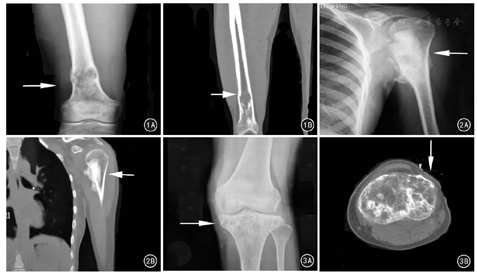

X线片表现:18例患者的X线影像显示,病变均起源于髓内。18例中,以溶骨性病变为主的4例,表现为病变部位骨密度明显降低、边界不清、少量成骨表现,均有皮质变薄、破坏甚至缺损征象,骨膜反应不明显,其中1例呈明显膨胀性改变、骨皮质毛糙,另1例病灶内可见粗大的骨小梁及骨皮质扇形样破坏。成骨性改变为主的3例,表现为大片形状不规则斑片状密度增高影,中央有密度稍低的改变,周围边界模糊,其中2例病变累及骨外。11例表现为溶骨与成骨混合存在,在X线片上呈虫噬样改变或呈云雾状骨密度增高伴有散在不同程度的低密度灶,大部分可累及骨皮质,其中5例可见明显骨膜反应、边界不清(图1A、图2A、图3A)。18例患者中,有13例具有2种以上的恶性征象,包括病灶边界不清、骨质破坏累及皮质、骨膜反应与软组织肿块。

CT表现:19例患者的CT影像17例有不同程度的恶性肿瘤征象,其共同特征是具有明显骨皮质破坏,病灶内可见肿瘤骨(图1B、图2B、图3B)。4例病灶以成骨表现为主,即为大团块状致密影或云雾状密度增高影,其内伴有散在低密度灶,其中2例穿透骨皮质,累及周围软组织;5例表现以溶骨破坏为主,即髓腔内呈虫蚀样破坏,累及骨皮质,其中1例表现为一侧骨皮质明显缺损、另外4例表现为骨皮质渗透性破坏(1例形成骨外病灶);1例表现为骨皮质破坏伴一侧明显硬化带形成;4例患者有明显的恶性征象,CT表现与高级别骨肉瘤相似,即骨皮质明显破坏伴骨膜反应、髓腔内有成骨表现;其余5例表现为不同程度的骨质破坏,破坏区域内散在少量斑片状密度增高影,部分伴有明显的骨膜反应。

X线作为骨科最常用的检查方法之一,在诊断LGCOS中扮演着重要的角色。但LGCOS患者的X线片表现各不相同,差异性较大,即有表现为良性病变倾向,又有表现为明显的恶性征象,主要表现为溶骨、成骨以及混合性病变。在Kurt等[3]报道的74例LGCOS患者中,61例X线片表现出边界不清、侵袭性破坏等恶性征象;肿瘤大小2~25 cm,平均9 cm,其中21例超过10 cm,10例小于5 cm。而Andresen等[6]研究的59例LGCOS患者中,27例表现为良性倾向,即未见肿瘤侵袭性征象,病灶大小为2~24(7.9±4.6 )cm 。笔者认为,LGCOS可能在早期时多呈现出良性病变的征象,随着疾病的进展,逐渐表现出侵袭性甚至明显的恶性征象。当X线检查难以判断肿瘤良恶性时,CT和MRI能够提供有效的帮助。CT具有更高的密度分辨率,能够更清楚地显示病变内的细节,特别是瘤骨的生成情况以及骨的破坏程度,甚至有学者认为混合型骨破坏是LGCOS中较为典型的表现[9]。MRI对于肿瘤累及的髓外病灶判断更加敏感,本组14例接受MRI检查的患者中,7例可见髓外病灶形成,累及周围软组织。MRI应用于LGCOS的诊断,可以更清楚地显示肿瘤累及的范围,尤其是对骨周围软组织的侵犯。笔者认为,MRI显示软组织病灶、骨膜反应、病变区域在造影剂下强化,是比较可靠的恶性征象,而病变周围水肿带可提示恶性可能。因此,经过X线片初步筛查,结合CT与MRI,能够明显提高LGCOS的诊断率。